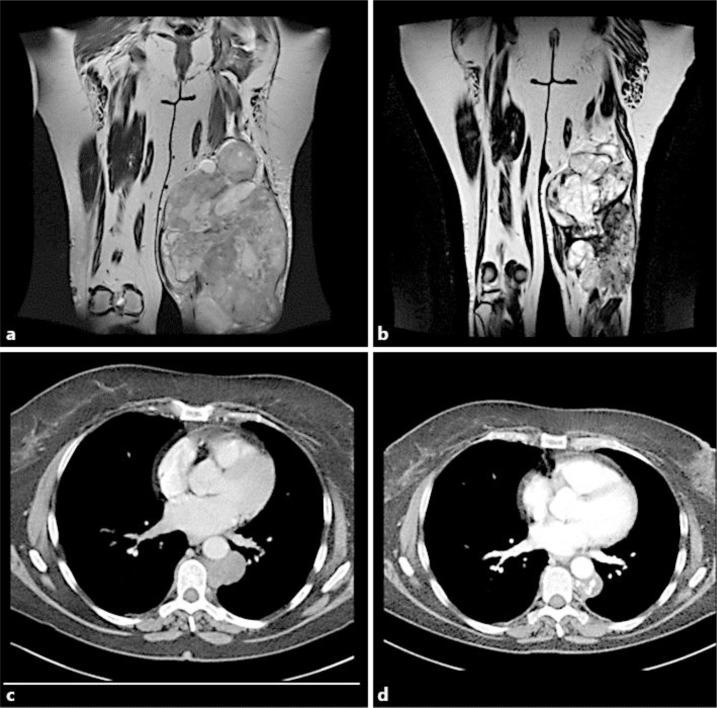

We report the case of a 63-year-old woman with a bulky and metastatic MRCL, treated with trabectedin 1.5 mg/m(2) as a first-line treatment. She experienced a long-lasting clinical benefit. The patients received 14 cycles of trabectedin and achieved a durable partial response to the metastases and a stable disease of the primary tumor, which is a very favorable safety profile. Also noteworthy is that we have observed a calcification of the primary tumor and the metastasis. The response, which lasted 30 months, led to a symptomatic improvement, associated with an excellent general condition and an absence of pain.

我们报告了一例63岁患有巨大转移性MRCL的女性患者,接受1.5mg/m²曲贝替定作为一线治疗。她获得了持久的临床获益。该患者接受了14个周期的曲贝替定治疗,对转移灶取得了持久的部分缓解,原发肿瘤病情稳定,安全性非常良好。同样值得注意的是,我们观察到原发肿瘤和转移灶出现了钙化。持续30个月的缓解带来了症状改善,患者总体状况良好且无疼痛。